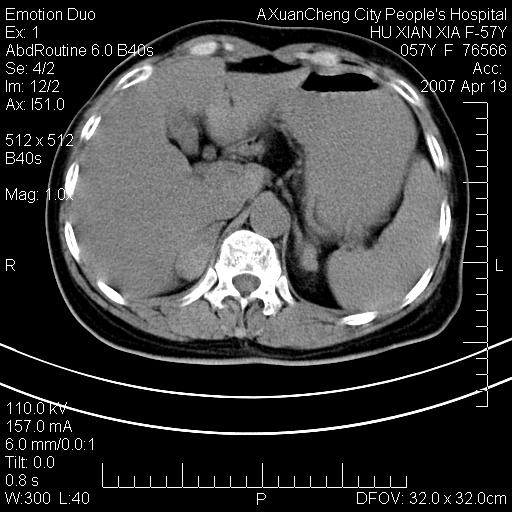

标题: CT7778:[原创]F,57Y腹痛待查,胸片提示肺部占位,应当很典型 [打印本页]

标题: CT7778:[原创]F,57Y腹痛待查,胸片提示肺部占位,应当很典型

胸片提示肺部占位

考虑:1、双侧肾上腺占位.2、肝左叶内侧段不规则低密度灶,建议强化扫描.

忽略了,只以为急腹症,应该支持肺癌肾上腺转移,肺癌患者20-30%发生肾上腺转移

双侧肾上腺增大,有分叶,密度均匀,考虑转移建议查原发灶

1.双侧肾上腺占位,转移首先考虑。

2.肝硬化,门静脉高压;肝左叶内侧段病灶建议增强。

3.12指肠水平段狭窄,建议行低张12指肠造影。

双侧肾上腺结节样肿块,结合肺部肿块,考虑肺癌肾上腺转移。

双侧肾上腺及腹膜后淋巴结增大,结合胸片提示肺部占位,考虑肺癌双侧肾上腺及腹膜后淋巴结转移.